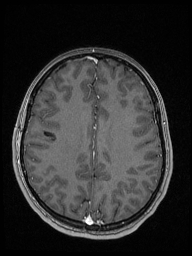

«Например, недавно в отделение поступил подросток с постепенно нарастающей очаговой неврологической симптоматикой. По результатам МРТ головного мозга была выявлена опухоль в функциональнозначимой зоне головного мозга (отвечающей за движение в конечностях) и без отчетливых границ с мозговой тканью. Открытое удаление новообразования могло привести к инвалидизации девочки, однако для определения дальнейшей тактики лечения требовался гистологический анализ патологической ткани с целью исключения злокачественного характера бластоматозного процесса. Было решено провести стереотаксическую биопсию с использованием нейронавигационной станции. Для проведения предварительных расчетов безопасной траектории прохождения биопсионной иглы до зоны-мишени (центральной части опухоли) в навигационную станцию были загружены данные МРТ обследования пациентки, затем в режиме реального времени были привязаны внешние анатомические ориентиры головы и лица. После компьютерной обработки полученных данных весь ход операции можно было контролировать на мониторе навигационной станции в трехмерном режиме. При помощи специальной биопсийной иглы были взяты образцы патологической ткани в намеченной зоне (что было подтверждено при контрольной МРТ)», — рассказывает заведующий отделением нейрохирургии для детей №7 к.м.н. Александр Вонгиевич Ким.

Визуализация введения иглы во время стереотаксической биопсии

Пациентка перенесла операцию удовлетворительно, осложнений в постоперационном периоде не было. Гистологический анализ подтвердил наличие опухоли, она оказалась доброкачественной, поэтому девочке не было показано онкостатическое лечение. Было лишь рекомендовано проходить регулярный МРТ контроль.

| МРТ до операции | МРТ после операции (1-е сутки после операции) | |